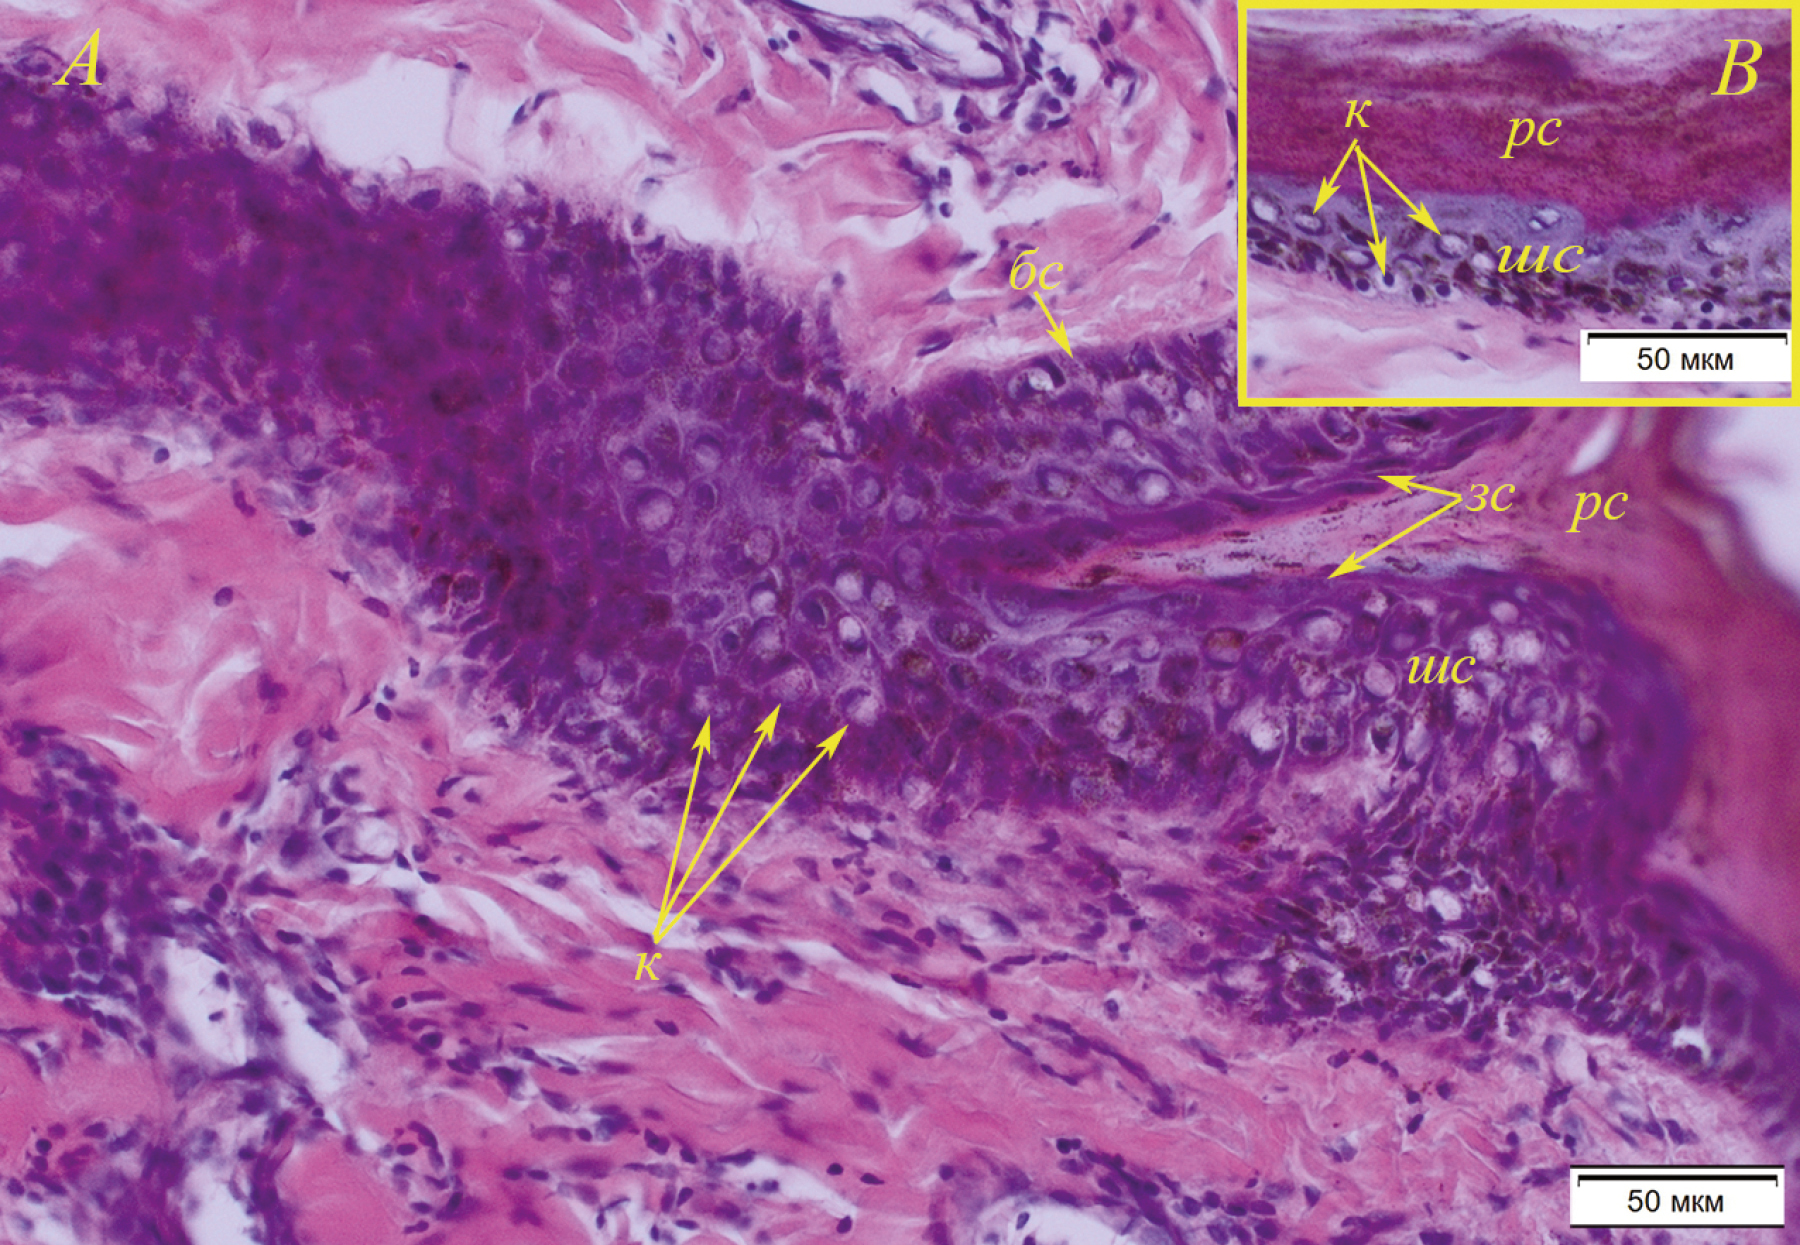

(1) Первый связан с появлением эпителиоцитов с признаками койлоцитоза (рис. 9). Койлоциты встречаются во всех слоях эпителия за исключением рогового. Цитоплазма патологичных клеток эпителия с перинуклеарным просветлением, клетки приобретают округлую форму. Ядро большинства койлоцитов имеет форму полумесяца, в таком случае оно лежит на периферии клетки, либо круглую форму, при этом оно конденсировано и расположено центрально. Также среди койлоцитов встречаются единичные клетки с признаками митоза. Койлоциты встречаются и в эпителии устья волосяных фолликулов на всем его протяжении, в том числе в корнях волос (рис. 10).

Рис. 9. Койлоцитоз в коже брюшной стенки (A; № 7, самец, 7+) и спины (B; № 4, самец, 1+) байкальской нерпы: рс – роговой слой эпителия, зс – зернистый слой (стрелки указывают на уплощенные веретеновидные клетки), шс – шиповатый слой, бс – базальный слой (указан стрелкой), к – койлоциты с лунообразными ядрами и койлоциты с центрально расположенным ядром (указывают стрелки). Окраска гематоксилином с эозином.